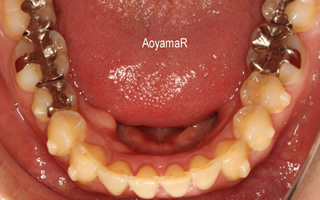

上顎前突(出っ歯、小さい下顎)の矯正症例

上顎歯列の遠心移動による非抜歯での上顎近心位、上顎前歯傾斜の改善

治療前

治療後